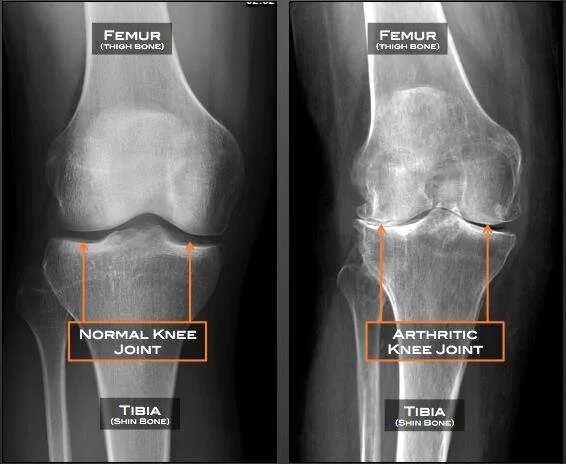

In addition to condition-specific articles, the blog delves into innovative treatment modalities and emerging trends in the field. Readers are introduced to advanced techniques such as epidural steroid injections, stem cell therapy for osteoarthritis, and multifaceted approaches to chronic pain management. These posts not only examine the benefits and potential risks of each treatment but also emphasize a holistic approach to patient care—integrating physical therapy, medication, and lifestyle modifications to achieve long-lasting relief.